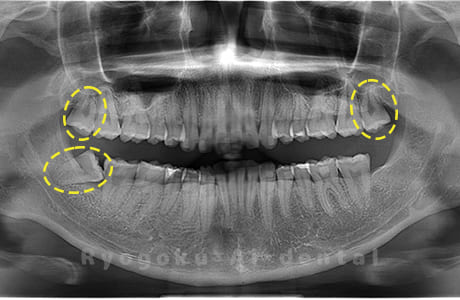

Case04

- 原因

- 上顎の親知らず、下顎の水平埋伏の親知らず

- 治療内容

- 上顎の親知らず、下顎の水平埋伏の親知らずを抜歯したケースです。

<リスク・副作用>

手術後は痛み、腫れ、痺れなどの副作用が生じる場合があります。